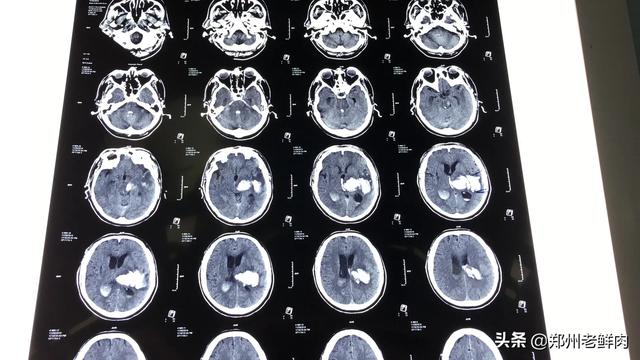

Je me suis occupé de patients souffrant d'hémorragies cérébrales et de lésions cérébrales, parfois trois ou quatre fois par jour, sauf que nous avons un chevet qui ne nécessite pas d'être accompagné par un membre de la famille, mais l'examen est nécessaire, le problème est que la prochaine fois que vous posez des questions, vous devez d'abord consulter le livre ?

7 jours pour faire une douzaine de fois CT ce peu importe dans quel hôpital régulier est impossible d'arriver les choses, pure absurdité. Aller à l'hôpital pour faire l'examen sont expressément prévus, ce qui implique également la question du remboursement de l'assurance médicale, de sorte que le bureau de l'assurance médicale va également effectuer la supervision et l'inspection. Les médecins n'osent pas le faire de manière inconsidérée, c'est se moquer de leur propre travail. Un examen tomodensitométrique normal, à moins qu'il ne soit nécessaire, est généralement espacé d'au moins un mois, l'intervalle est long afin d'établir un jugement comparatif sur l'état de santé, de voir si le traitement n'a pas d'effet, il n'est pas possible de gagner de l'argent en effectuant un examen tomodensitométrique sans discernement, le bureau de l'assurance médicale ne peut pas passer. Pour être honnête, l'hôpital veut gagner de l'argent sur votre dos, il y a des moyens de vous faire passer inaperçu, il est impossible d'utiliser ce genre de moyen stupide que tout le monde connaît, vous ne pouvez donc que vous attirer des ennuis.